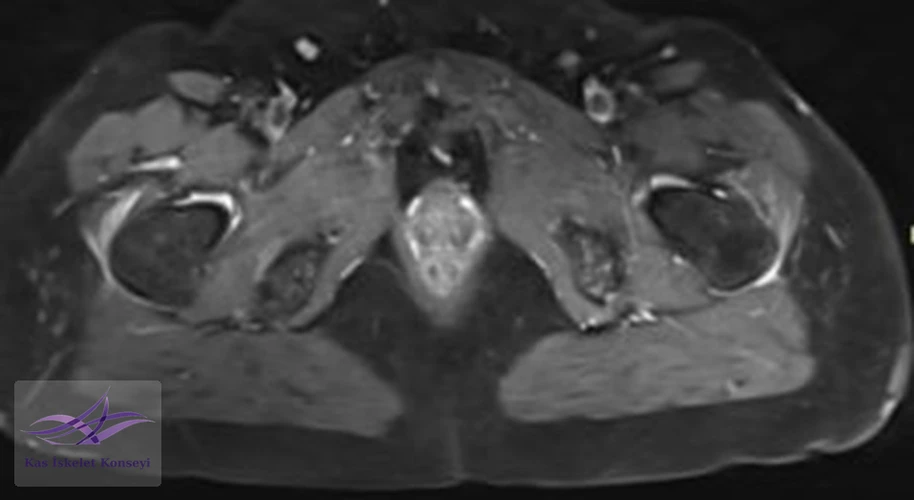

Resim 5. Kalça MRG, aksiyal kesit.